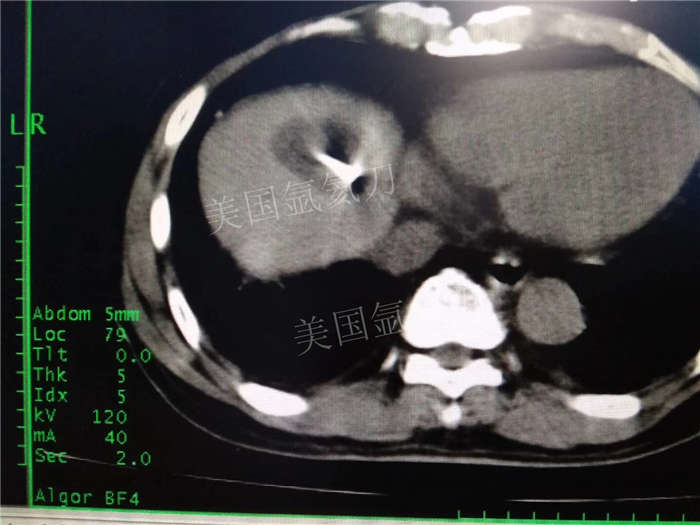

博罗人民医院乙状结肠癌术后肝转移化疗后冷冻消融